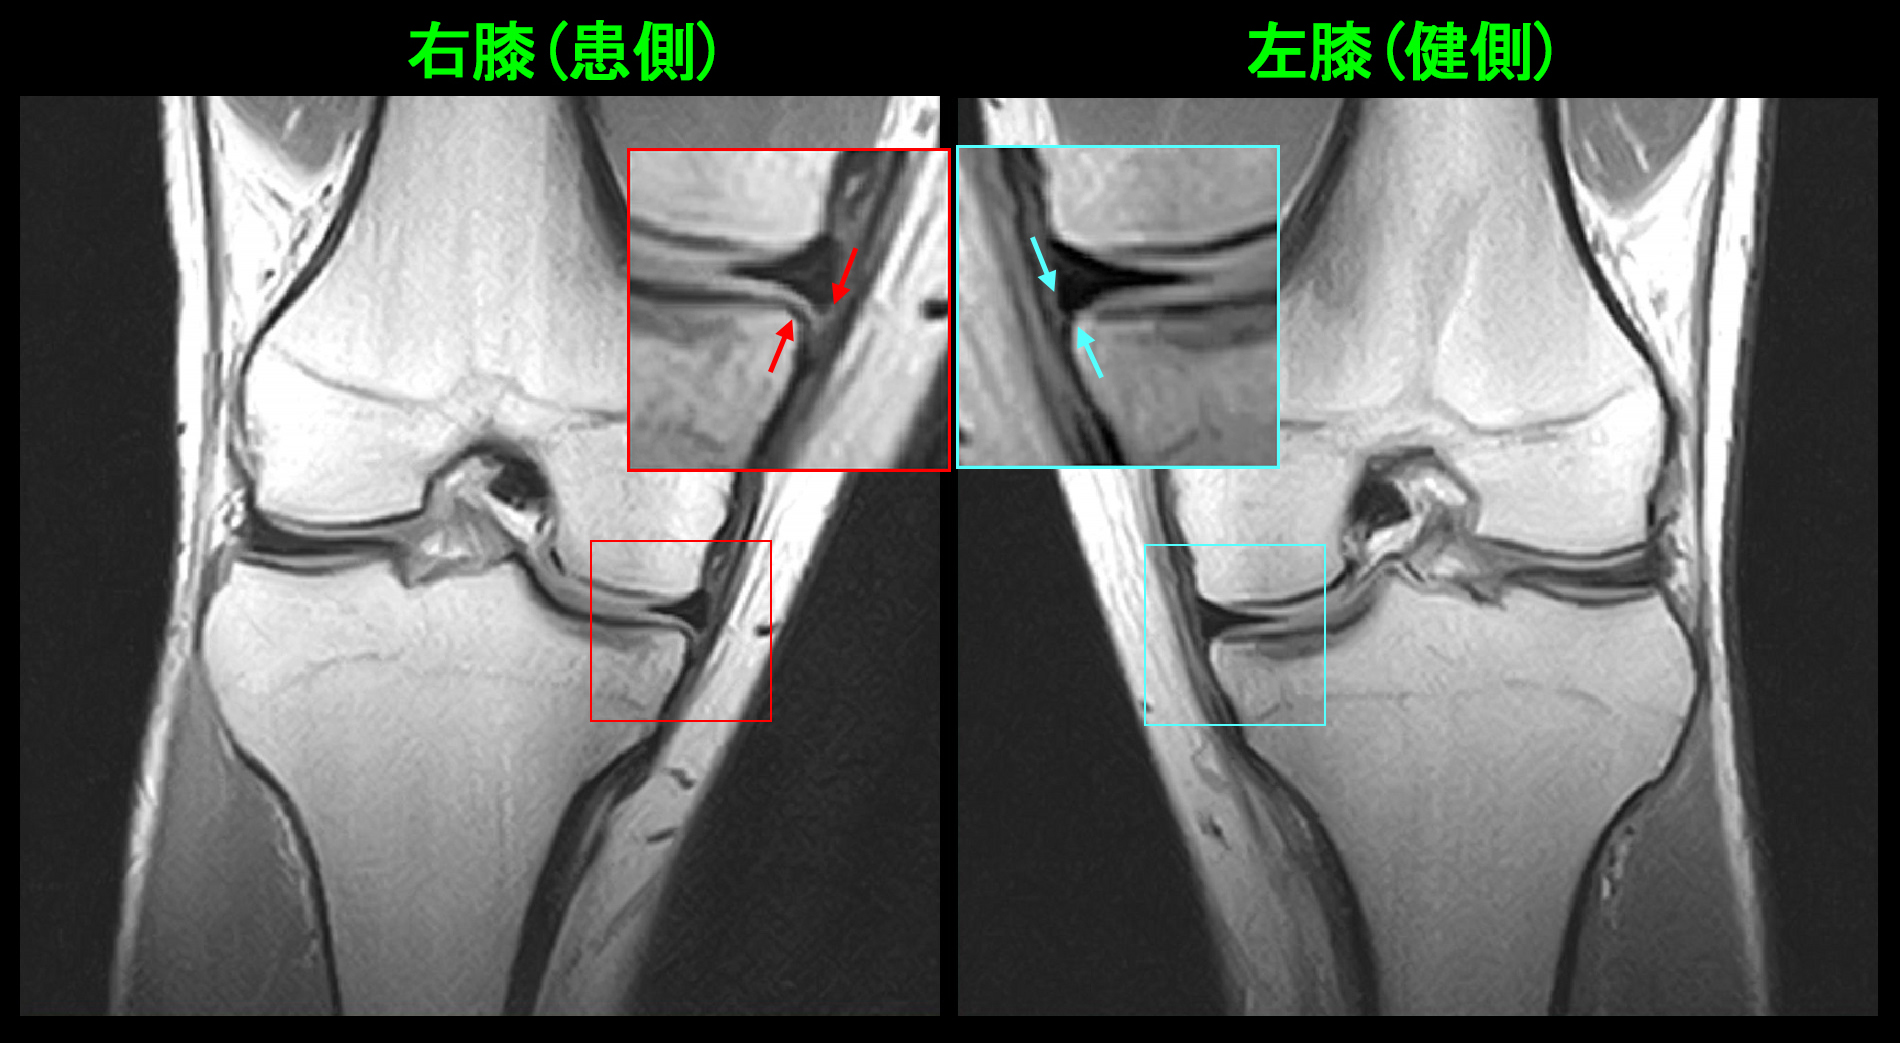

18才の高校3年生の女子生徒です。令和7年9月6日自転車での学校帰りに同じ方向に走っていた車が左折してきて、それを避けようとして左側に転倒し、左膝を打撲しました。9月7日他整形外科受診して、打撲の診断でシップと投薬を受け、服薬は有効だったそうですが、服薬終了で左膝痛は悪化したそうです。以後時々左膝痛があり、10月12日さらに症状は悪化し、左膝屈曲で痛み、椅座位でも痛みがあるということで、10月25日に当院を受診されました。しかし、卓球での痛みはVAS4というので大したことないという印象でした。

18才女 MR1.jpgPDの冠状断の左膝の中央部分では軽度の亜脱臼を認める所見でした。この内側半月板所見は注意深く観察しなければ、見落としても仕方ないような所見です。

18才女 MR3.jpg

PDの矢状断(横から見た所見)でも左半月板前方部は軽微な亜脱臼を示していました。この程度の亜脱臼の所見ならば、服薬で良くなるであろうと推察し、鎮痛剤のロキソニン2錠とプレドニン2.5㎎2錠を朝夕で1週間、2週目は鎮痛剤のメロキシカム1錠とプレドニゾロン2.5㎎朝1錠で対応しました。40代50代の加齢性の症状でもこの薬剤の服用で症状は軽減することが多くあります。